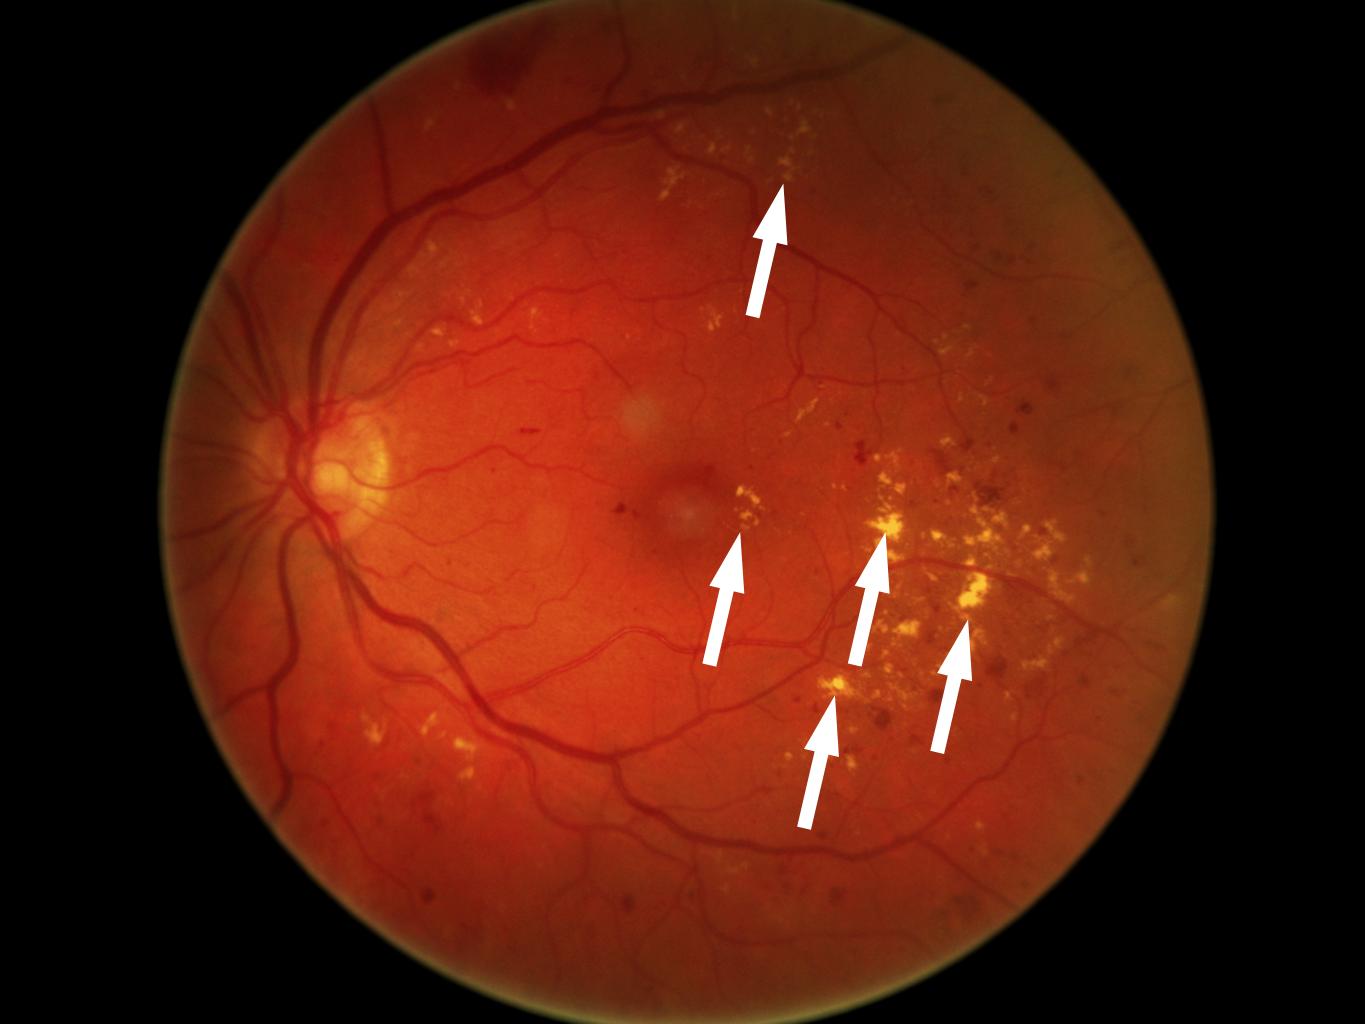

1. Рис.1 | |

2. Рис.2 | |

3. Рис.3 | |

4. Рис.4 | |

5. Рис.5 | |

6. Рис.6 | |